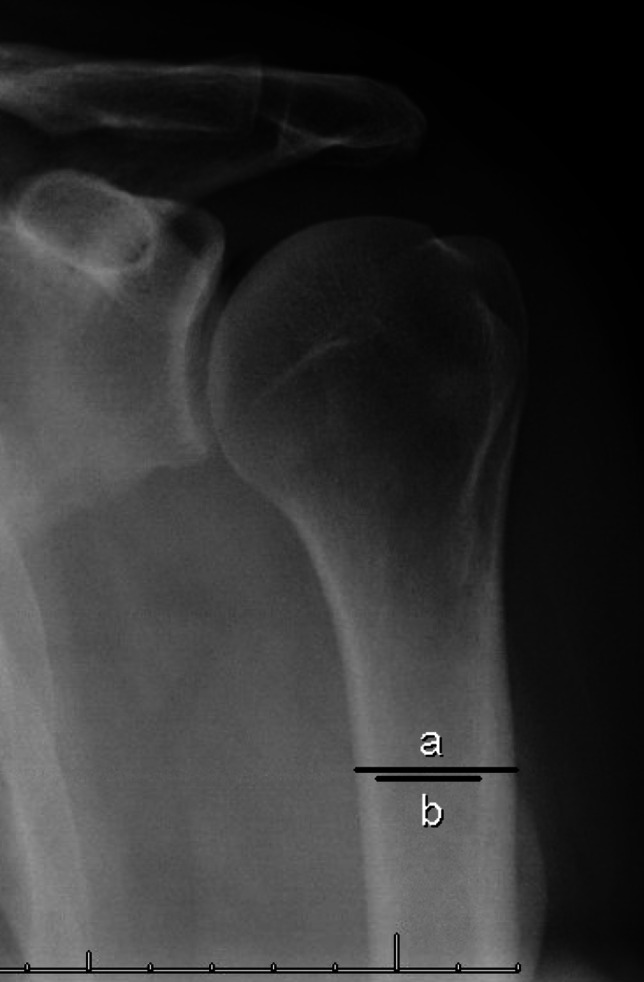

Recent findings: Emerging data surrounding perioperative use of anti-osteoporosis medications for patients undergoing shoulder surgery have not shown definitively favorable or unfavorable outcomes. Similar evaluations in animal studies have shown promising results as a biologic augment to tendon and bone healing, especially with newer, anabolic agents. The mainstay of bone health management remains pre-operative evaluation, using opportunistic radiographic and CT based validated measurements, along with optimization of risk factors. Surgical techniques continue to incorporate implants that perform well in osteopenic bone. Promising pre-clinical studies have identified anabolic anti-osteoporosis medications as viable biologic augments to shoulder surgery, which has not been borne out in any clinical studies at this time.